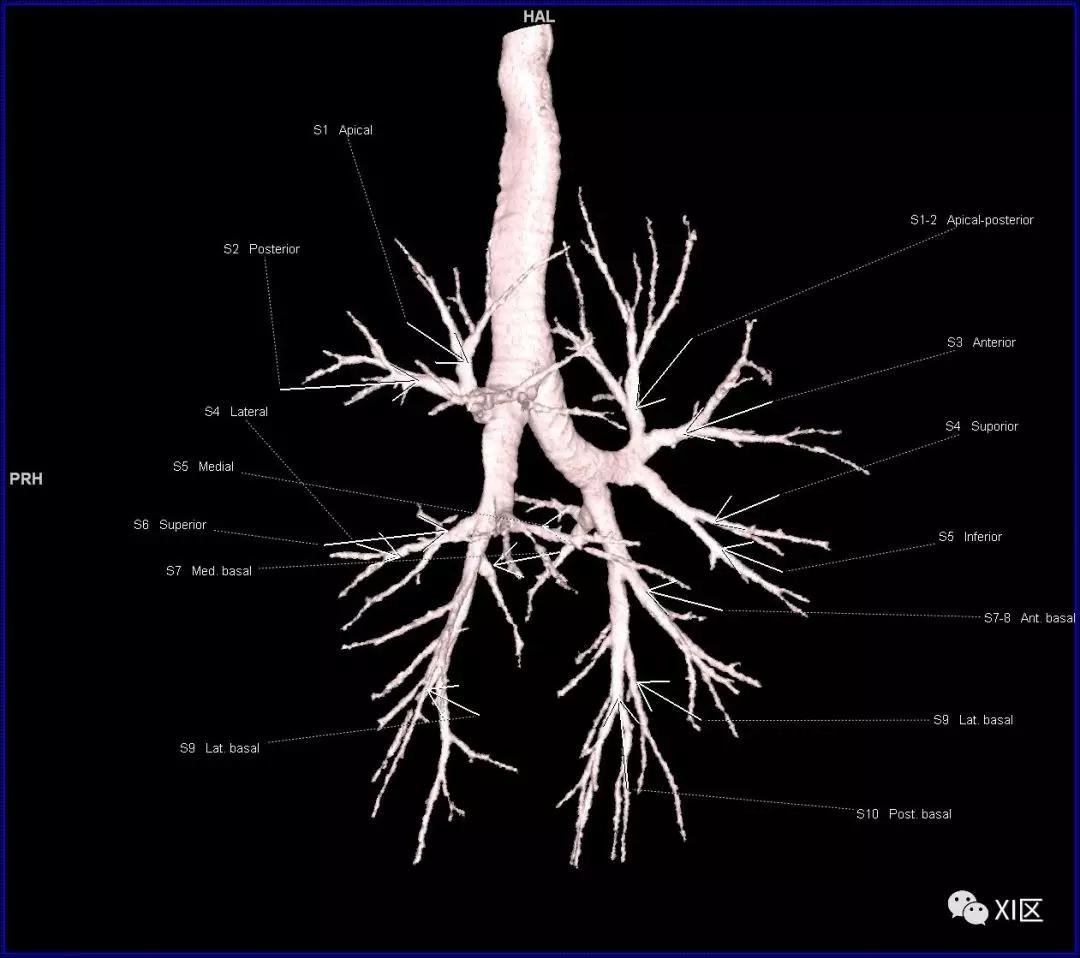

段支气管的命名(图片源自网络)

段支气管的命名

肺的分段

肺的分段示意图(图片源自网络)

在进行肺的分段时,可以上下观察浏览,沿着相应气管的走形可以更容易准确地进行分段。